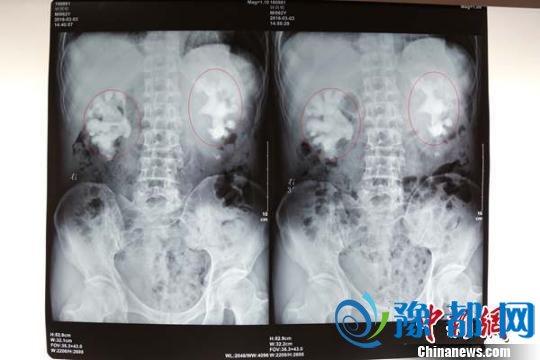

钟大爷的第一次DR(数字放射成像)检查结果,图中像“生姜”的即患者的巨大肾结石。陈松摄

中新网成都5月20日电 (陈松胡敏)肾结石是在医学上一种常见的、多发的泌尿系统疾病。但是对于年过六旬的钟详(化名)来说,苦不堪言,因为他双肾的结石足有两片生姜大。

经人推荐,钟大爷来到四川结石病医院。“这块头,要是能整块拿出来,肯定不比菜市场的生姜小!”日前,钟大爷在四川结石病医院接受了治疗,当该院医生见到给患者拍摄的X光片时,见多识广的医生们也为这巨大的结石感到惊叹。

据四川结石病医院主任医师、泌尿二科主任常立高介绍,像钟大爷如此巨大的双肾铸型结石,在他数十年的行医生涯中是较为少见的,由于患者结石过于巨大,且充满了其肾内空间,且无法接受开放式手术取石,处理起来十分麻烦。